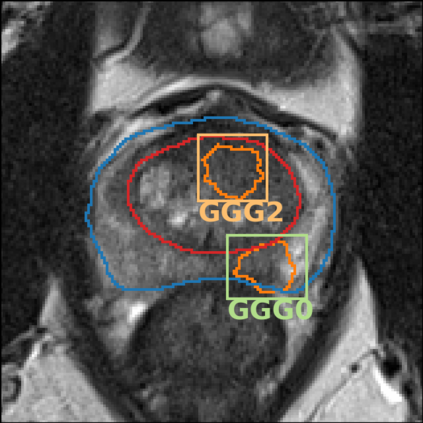

The emergence of multi-parametric magnetic resonance imaging (mpMRI) has had a profound impact on the diagnosis of prostate cancers (PCa), which is the most prevalent malignancy in males in the western world, enabling a better selection of patients for confirmation biopsy. However, analyzing these images is complex even for experts, hence opening an opportunity for computer-aided diagnosis systems to seize. This paper proposes a fully automatic system based on Deep Learning that takes a prostate mpMRI from a PCa-suspect patient and, by leveraging the Retina U-Net detection framework, locates PCa lesions, segments them, and predicts their most likely Gleason grade group (GGG). It uses 490 mpMRIs for training/validation, and 75 patients for testing from two different datasets: ProstateX and IVO (Valencia Oncology Institute Foundation). In the test set, it achieves an excellent lesion-level AUC/sensitivity/specificity for the GGG$\geq$2 significance criterion of 0.96/1.00/0.79 for the ProstateX dataset, and 0.95/1.00/0.80 for the IVO dataset. Evaluated at a patient level, the results are 0.87/1.00/0.375 in ProstateX, and 0.91/1.00/0.762 in IVO. Furthermore, on the online ProstateX grand challenge, the model obtained an AUC of 0.85 (0.87 when trained only on the ProstateX data, tying up with the original winner of the challenge). For expert comparison, IVO radiologist's PI-RADS 4 sensitivity/specificity were 0.88/0.56 at a lesion level, and 0.85/0.58 at a patient level. Additional subsystems for automatic prostate zonal segmentation and mpMRI non-rigid sequence registration were also employed to produce the final fully automated system. The code for the ProstateX-trained system has been made openly available at https://github.com/OscarPellicer/prostate_lesion_detection. We hope that this will represent a landmark for future research to use, compare and improve upon.